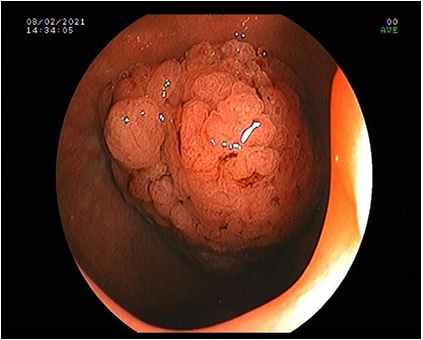

Solitary duodenal hamartomatous polyp in ninth decade of the life: A case report